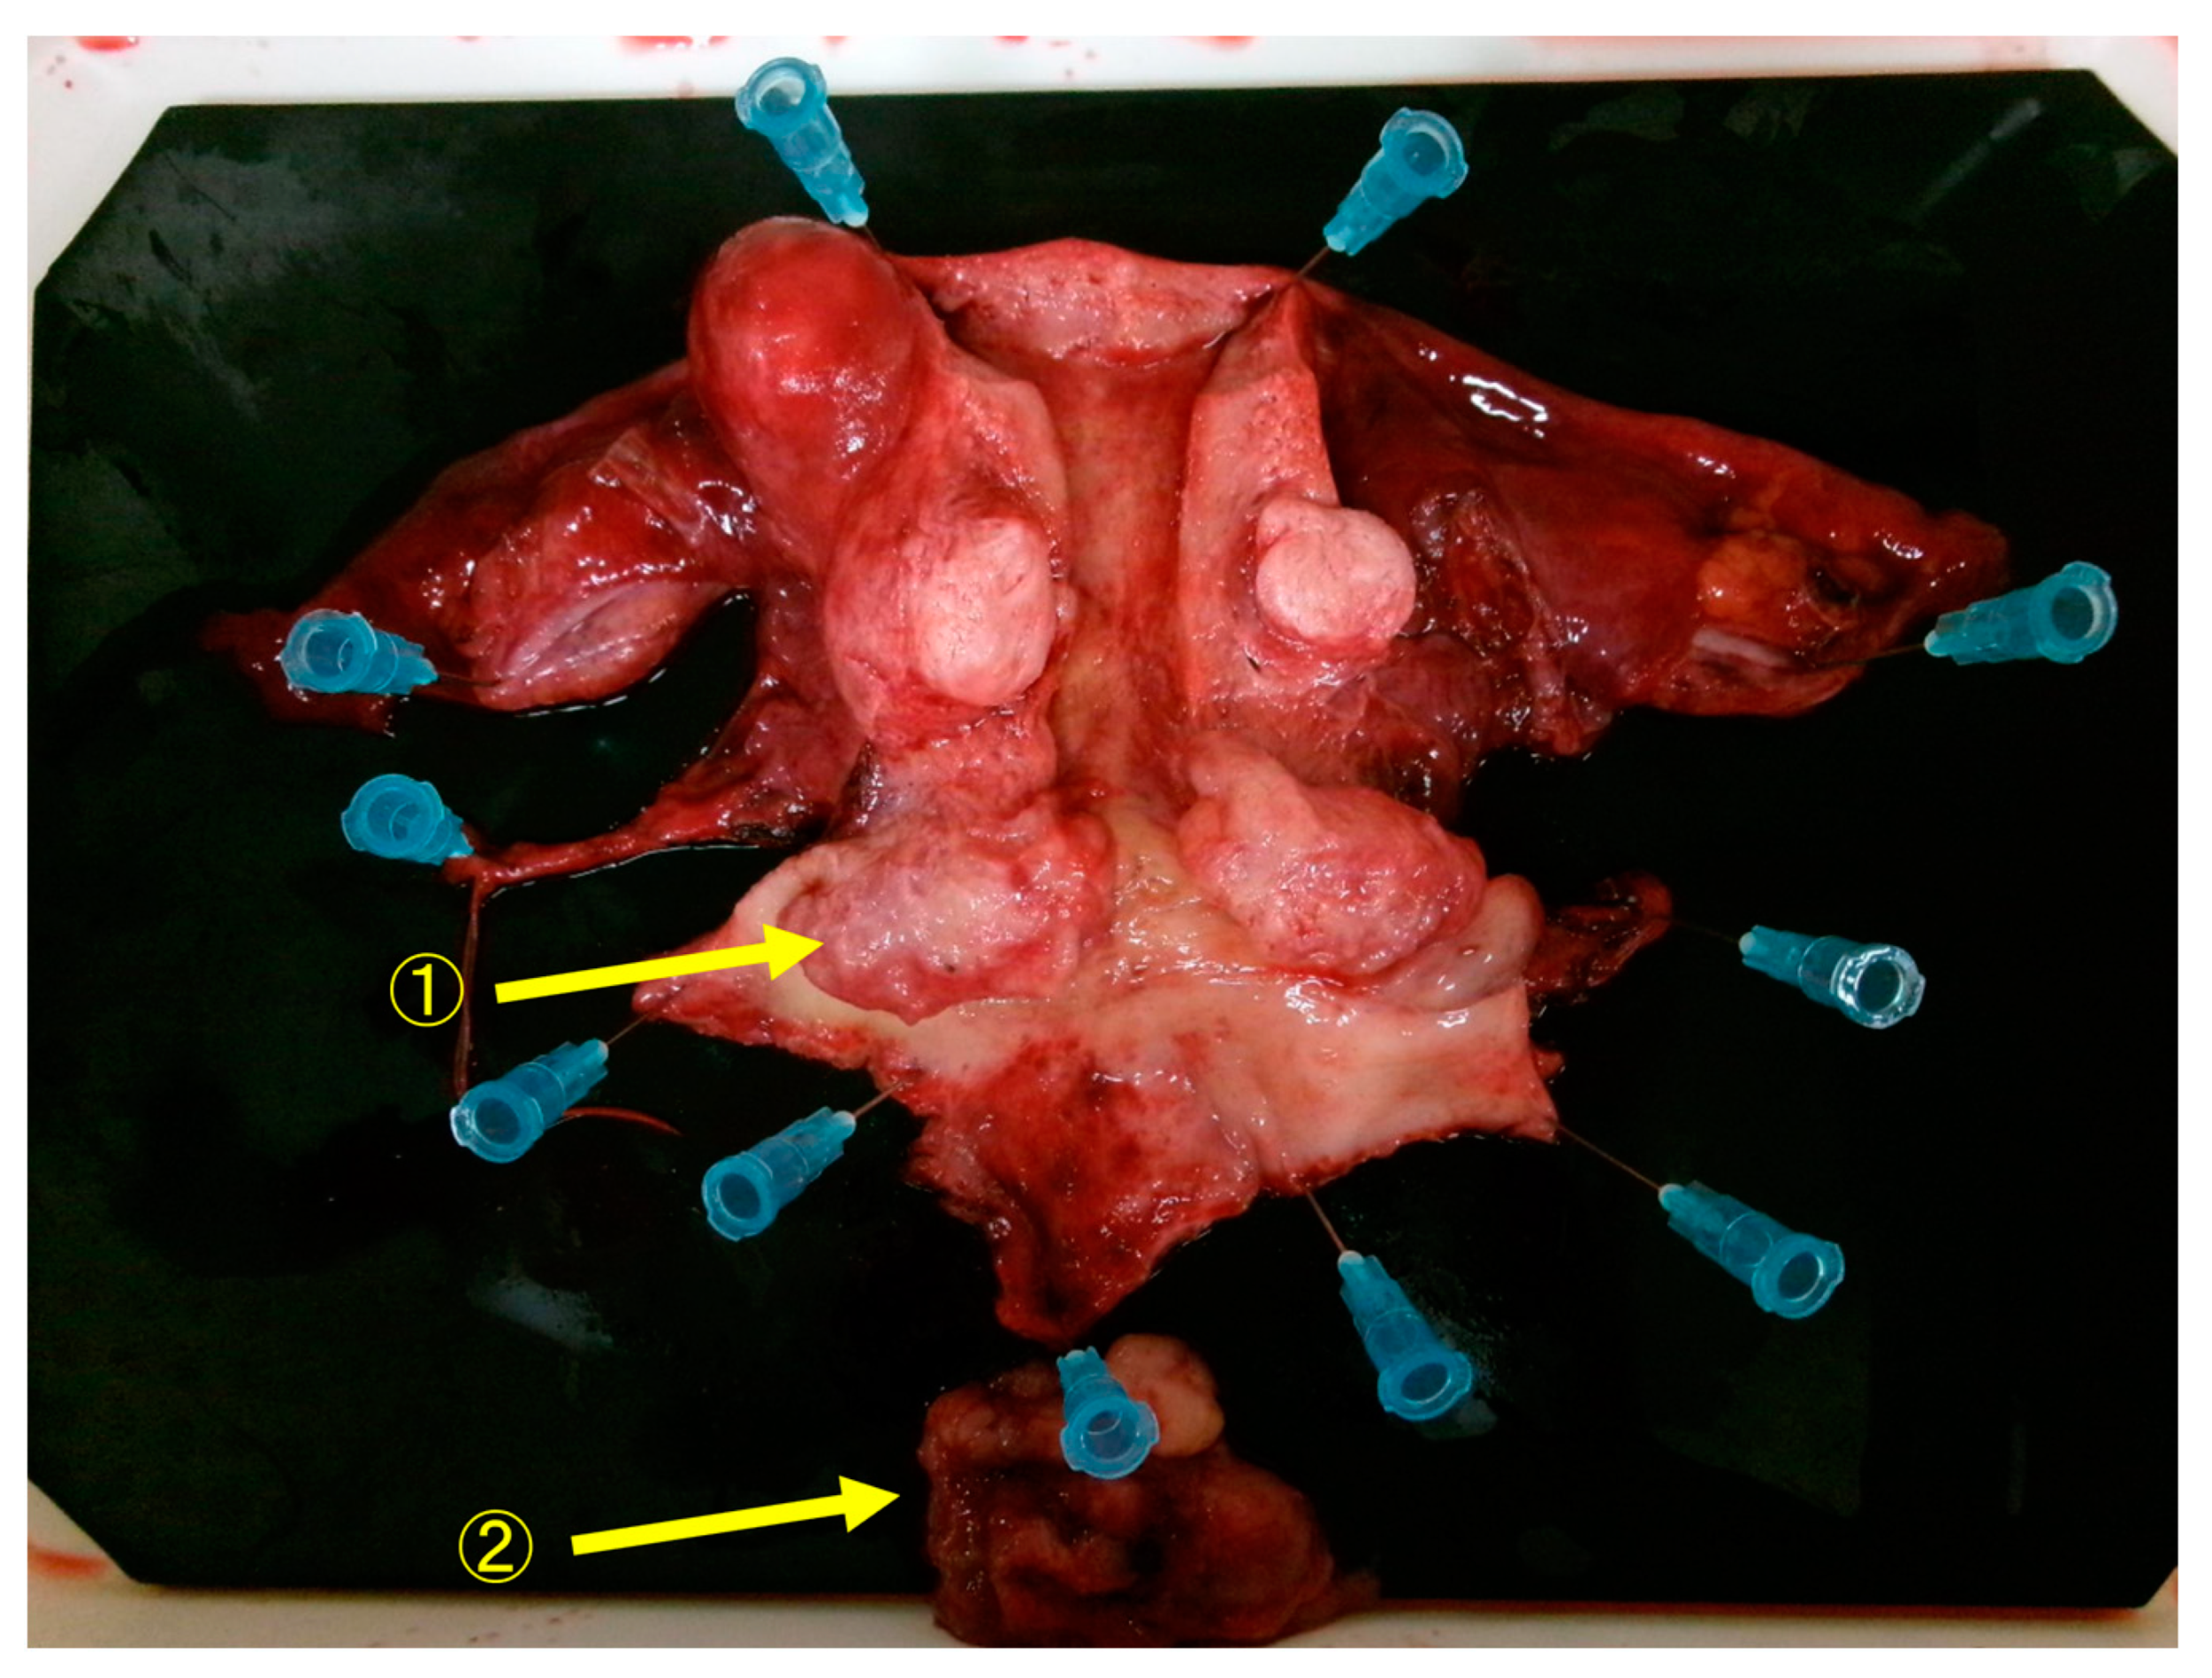

Figure 4.

Macroscopic findings of the resected specimen showed that the resection margins between the tumor and the parametria were negative, and the resection was diagnosed as complete. ① Cervical tumor. ② Tumor that has fallen off from the cervical tumor.